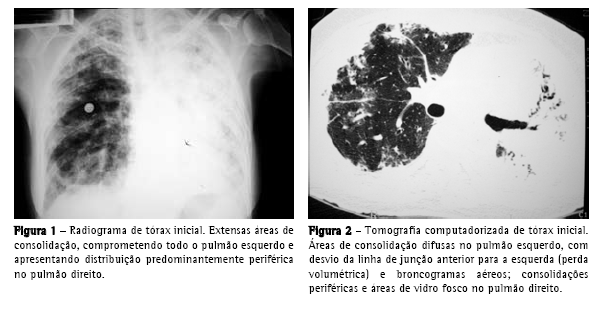

Initial chest X-ray (Figure 1): extensive areas of consolidation throughout the left lung and with predominantly peripheral distribution in the right lung;

Initial computed tomography scan of the chest (Figure 2): diffuse areas of consolidation in the left lung (with volumetric loss and air bronchograms), peripheral consolidations, and areas of ground-glass attenuation in the right lung;